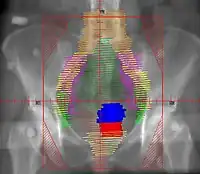

El tratamiento específico para cada mujer depende del tipo de cáncer que se haya desarrollado en su vagina y del grado de infiltración que tenga.[1] Se ha usado la radioterapia y la extirpación del cáncer quirúrgicamente. Si el tumor se originó en el endometrio y se extendió hacia la vagina pueden añadirle quimioterapia al tratamiento. En otros casos el especialista puede decidir combinar los tres métodos: cirugía, quimioterapia y radioterapia.[5]